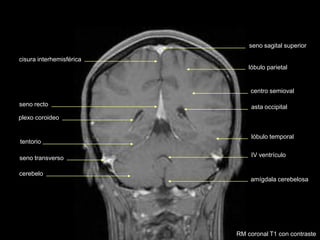

RM coronal T1 con contraste

pineal

seno sagital superior

cisura interhemisférica

asta occipital

centro semioval

IV ventrículo

tentorio

cerebelo

amígdala cerebelosa

plexo coroideo

lóbulo parietal

lóbulo temporal

seno transverso

seno recto